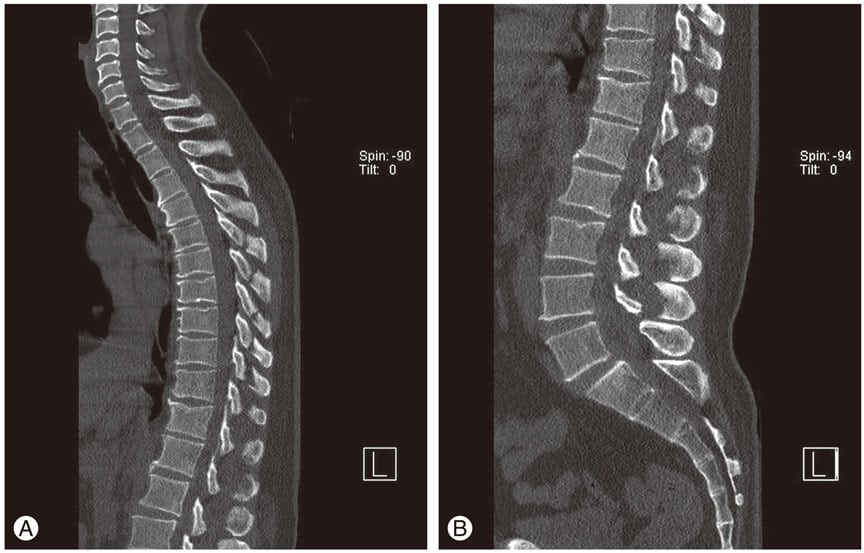

Остеохондроз на МРТ.

Какой врач лечит остеохондроз, зависит от укомплектованности штата больницы. Поэтому человек с участившимися болями в шее, груди, пояснице чаще всего записывается на прием к терапевту или семейному доктору. Они обладают всеми навыками диагностирования патологии, а при отсутствии врачей узкой специализации занимаются лечением остеохондроза 1 или 2 степени тяжести. Перед началом терапии проводится ряд инструментальных и лабораторных исследований:

- рентгенография;

- КТ или МРТ;

- биохимический анализ крови.

Остеохондроз на рентгене.

- Рентген показывает, какое место позвоночника подверглось дистрофическим изменениям и степень этого поражения, выявляет наличие смещенных дисков, образование наростов (остеофитов). Обычно делается в 2-х проекциях.

- МРТ и КТ проводится после рентгена для уточнения состояния межпозвоночного диска, выявления новообразований. Данные методы дорогостоящие, нет возможности применять их для всех пациентов.